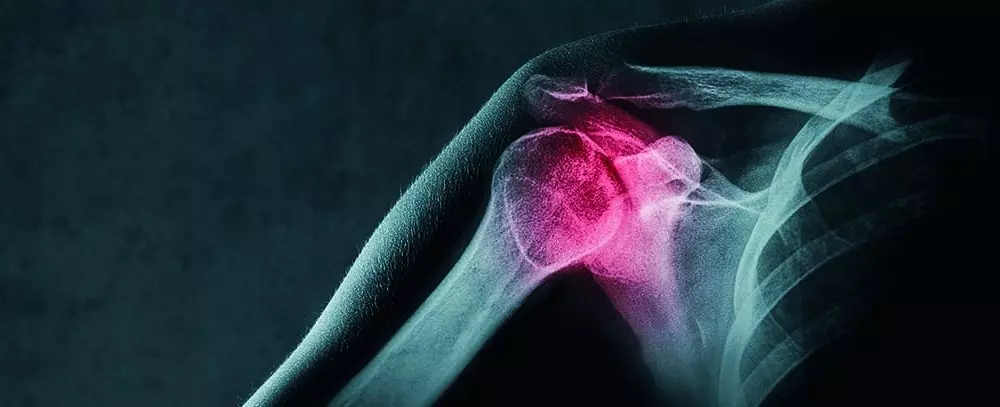

- urazach w obrębie stawu kolanowego,